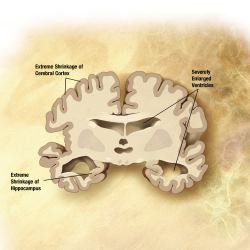

Alzheimer’s disease is an irreversible, progressive brain disorder that afflicts more than 6.5 million Americans. It slowly destroys memory and cognitive skills and, eventually, the ability to perform even simple tasks. Although the specific causes of Alzheimer’s are not fully understood, it is characterized by changes in the brain, including the formation of various abnormal structures that result in the loss of neurons and their connections.